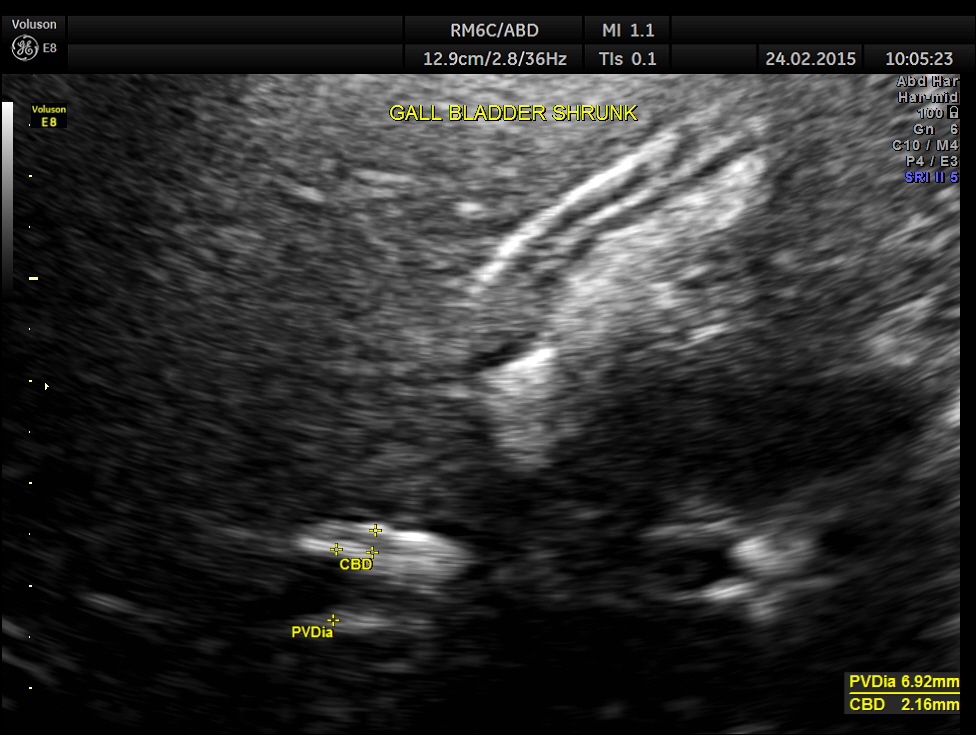

Completely collapsed and shrunk gall bladder in spite of over night fasting.

This patient probably had a functional gall bladder abnormality , asymptomatic at present.

Contrary to expectations she had a collapsed gall bladder in the fasting status and a partial filling up of bile after a fatty meal. As she had no symptoms , she was advised periodic follow up once in 6 months to start with.

The text book advised procedure to confirm functional gall bladder abnormality is CCK ( cholecystokinin) stimulated cholescintigraphy. But examining a patient after a fatty meal with ultrasound could be an alternative in places where this facility is not available or for cost effectiveness.